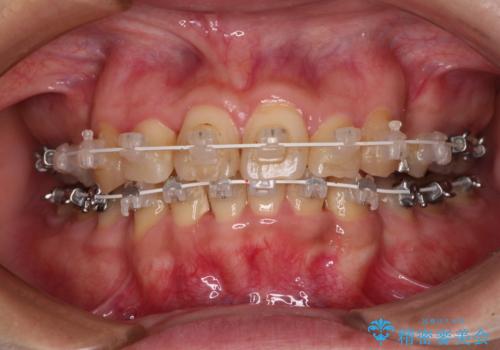

- 海外で抜歯矯正を開始し、治療途中で帰国したため、転院先を探しているとのことで来院された患者様です。

ワイヤーは抜けてしまい、後戻りが始まっている状態でしたが、既存の装置を継続利用して受け入れてくれる医院が見つからないとのことでした。

当院では、張り替える必要のある部位は張り替えることで継続することとし、抜歯スペースを閉じていくように治療を行うこととしました。